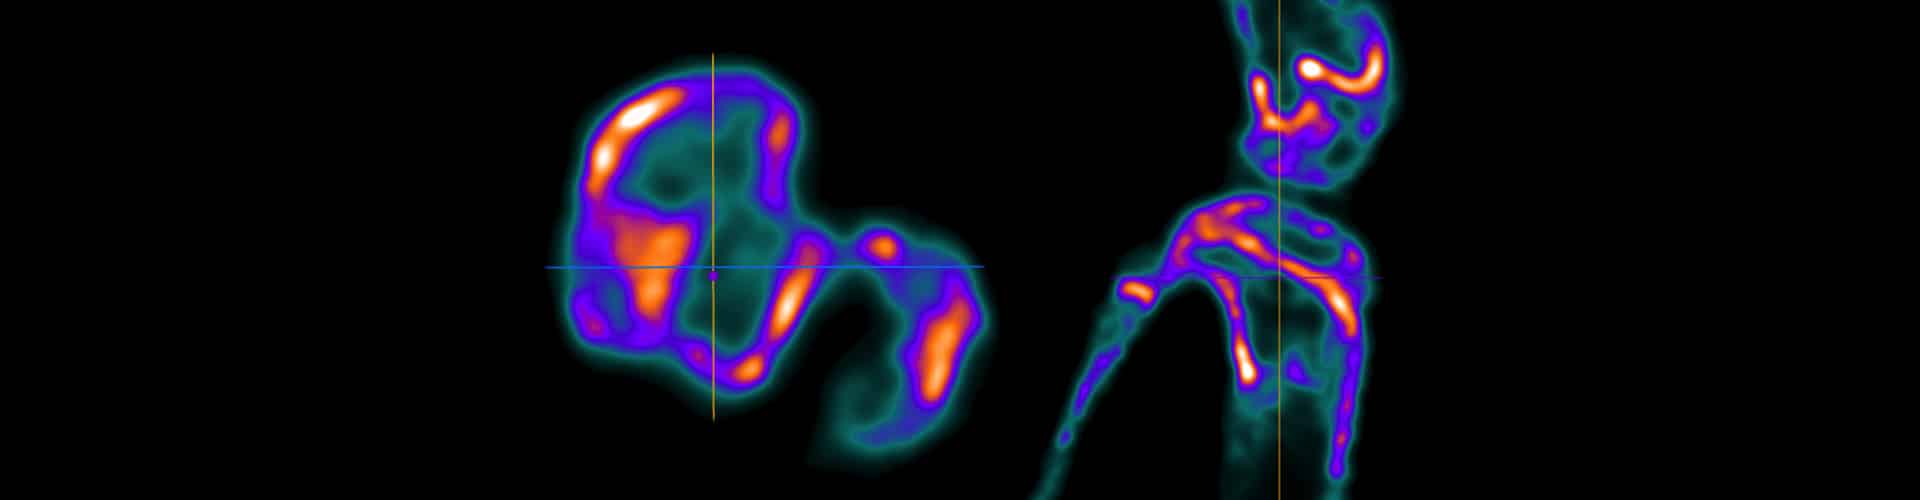

3D Autoradiography enables high-resolution, ex vivo visualization and quantification of radiotracer distributions in intact samples. By reconstructing volumetric datasets rather than relying on thin tissue sections, researchers gain clearer spatial context, improved accuracy, and stronger translational relevance for molecular imaging studies.

- EUltra-high spatial resolution down to 0.12 mm for detailed molecular localization

- EFlexible digital re-slicing for multi-angle tissue analysis and interpretation

When combined with ultra-high-resolution CT, EXIRAD-3D enables accurate overlay of molecular autoradiography data with anatomical structures. This integration improves localization, interpretation, and confidence in tissue-level analysis, supporting deeper insight into biological systems and tracer behavior.